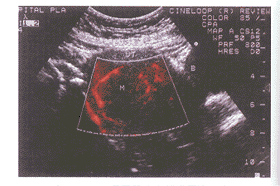

彩色多普勒能量显像检测子宫肌瘤内血流的应用价值

摘 要 目的:根据对46例患者54个瘤体经腹及经阴道途径的扫查结果,本文探讨了彩色多普勒能量显像检测子宫肌瘤内血流的应用价值。方法:对46例患者54个瘤体经腹壁及经阴道途径联合扫查。结果:经腹壁扫查时,40.7%的CDFI显示内部或周边有血流信号 ......